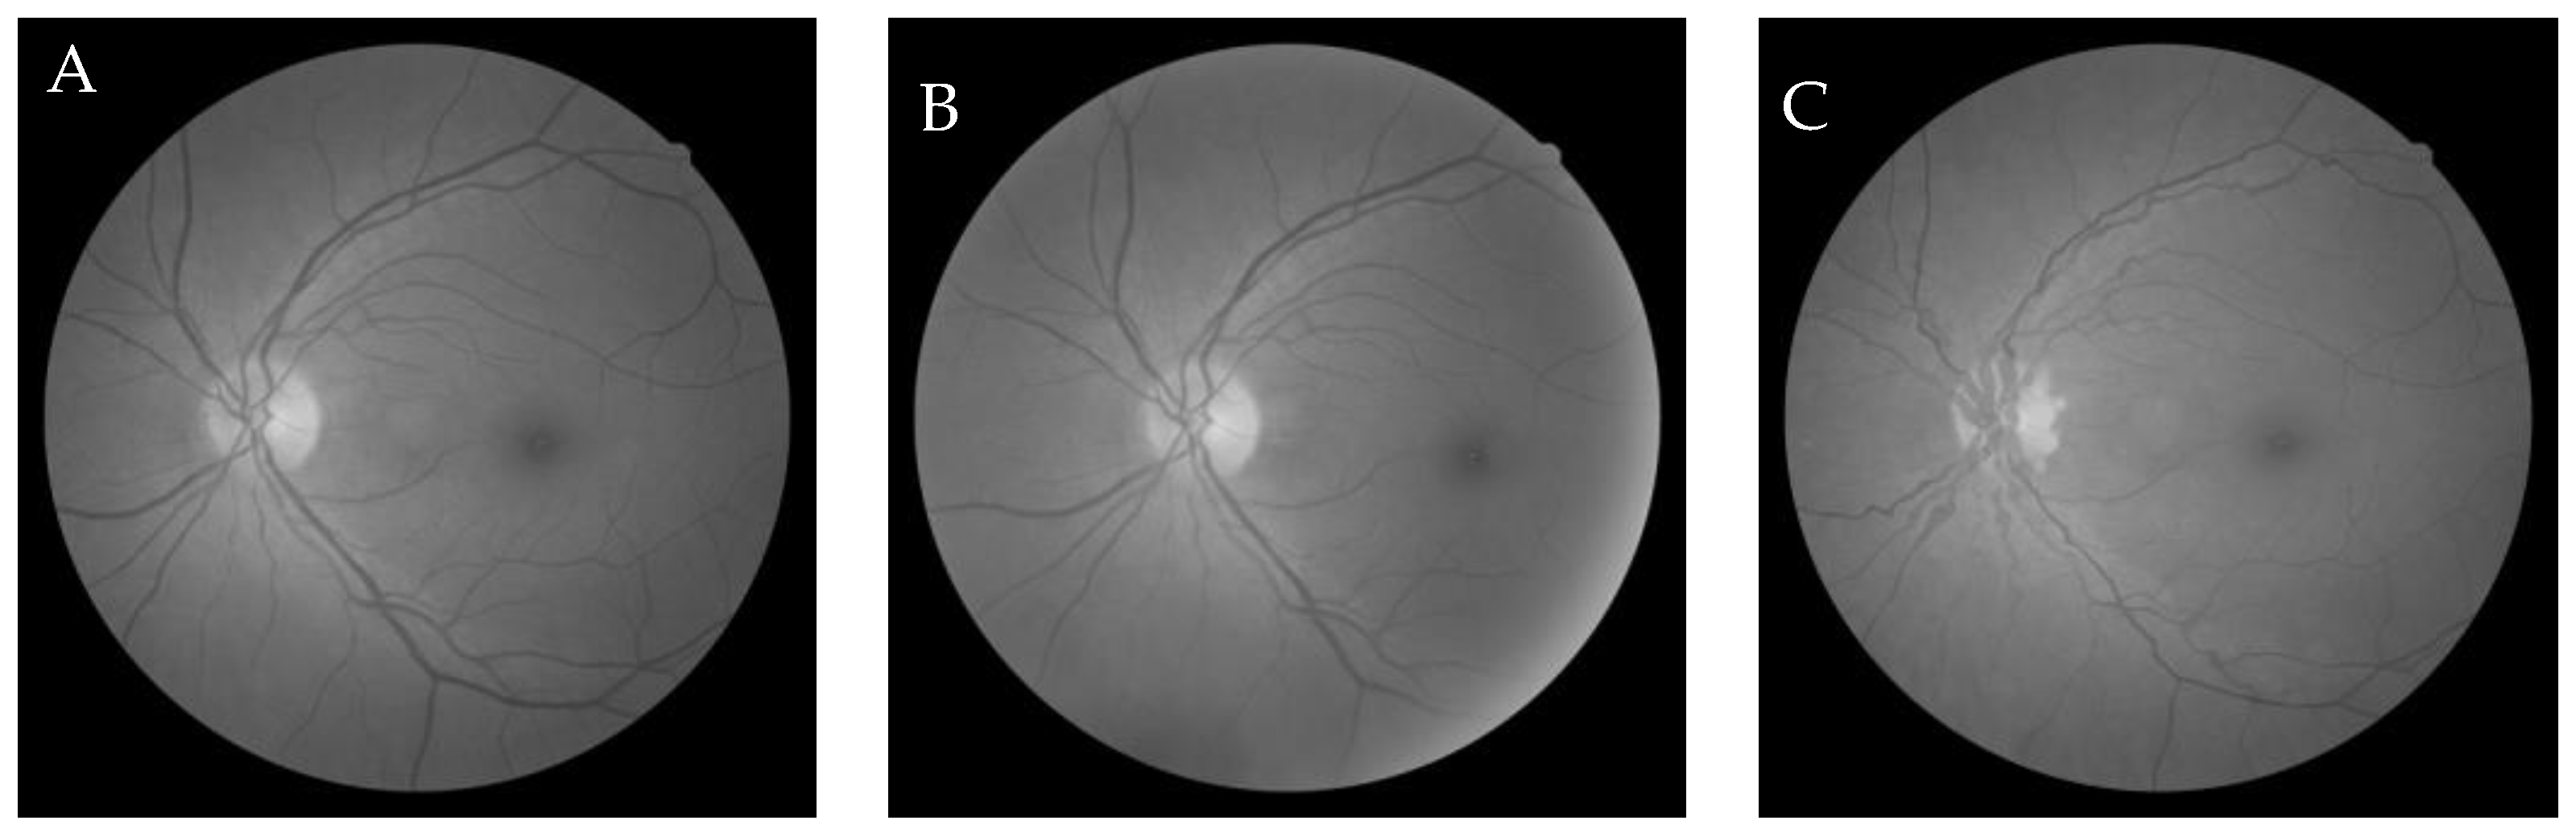

6.1. Dataset

6.2.1. Grey-Wolf Optimization-Based Wang’s Demons Registration